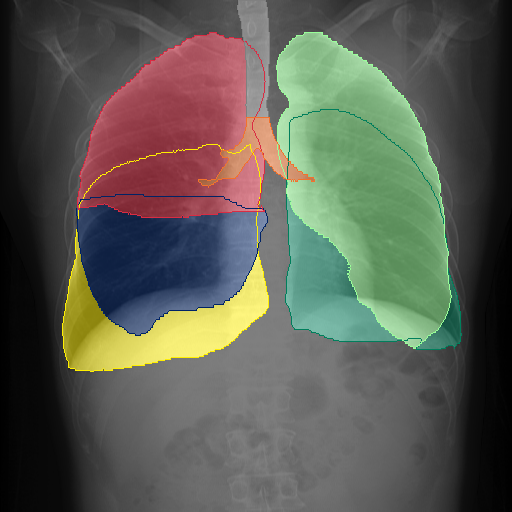

We display qualitative results in Fig. 3. The annotators tend to be content with most annotations. There are edits at the extensions of the esophagus, trachea, and aorta and corrections of the lower ribs. There is little consensus for classes in the abdominal area, such as the stomach, as seen on the right of Fig. 3 . In contrast, the annotators often align for bone classes.

We show the quantitative segmentation performance against medical expert annotations for all classes in Fig. 3 . The dashed lines represent the IAA, whereas the dotted line displays the average MAA. As the task for the human annotators was not to annotate from scratch but to correct wrong pixel-wise predictions, we can see a high MAA for most classes. In the frontal view, the most significant disagreements exist for rare bone structures such as L3 and C4, lower ribs, the mediastinal distribution, or the breast tissue. The IAA and MAA are highly similar with mIoU of respective 95% and 94%. The Hausdorff distance for MAA is slightly lower than the IAA, indicating slight differences in boundary annotations while maintaining a considerable overlap with the other annotator. In the lateral view, the concrete delineation of rib structures appears ambiguous, leading to lower MAA and IAA with a greater IAA than MAA for all metrics in this supercategory. Overall there is less agreement between the medical experts in the lateral view, leading to a better average MAA than IAA across all metrics (i.e. 85% vs 83% mIoU). While the experts propose changes to the original predictions, they are often not overlapping. In the lateral view, rib segmentations can become quite hard to interpret. While both annotators disagree with the rib segmentations, they do not always agree on how they should look. Similarly to the frontal view, tube-like structures like the esophagus are extended as they can appear fractured at times.